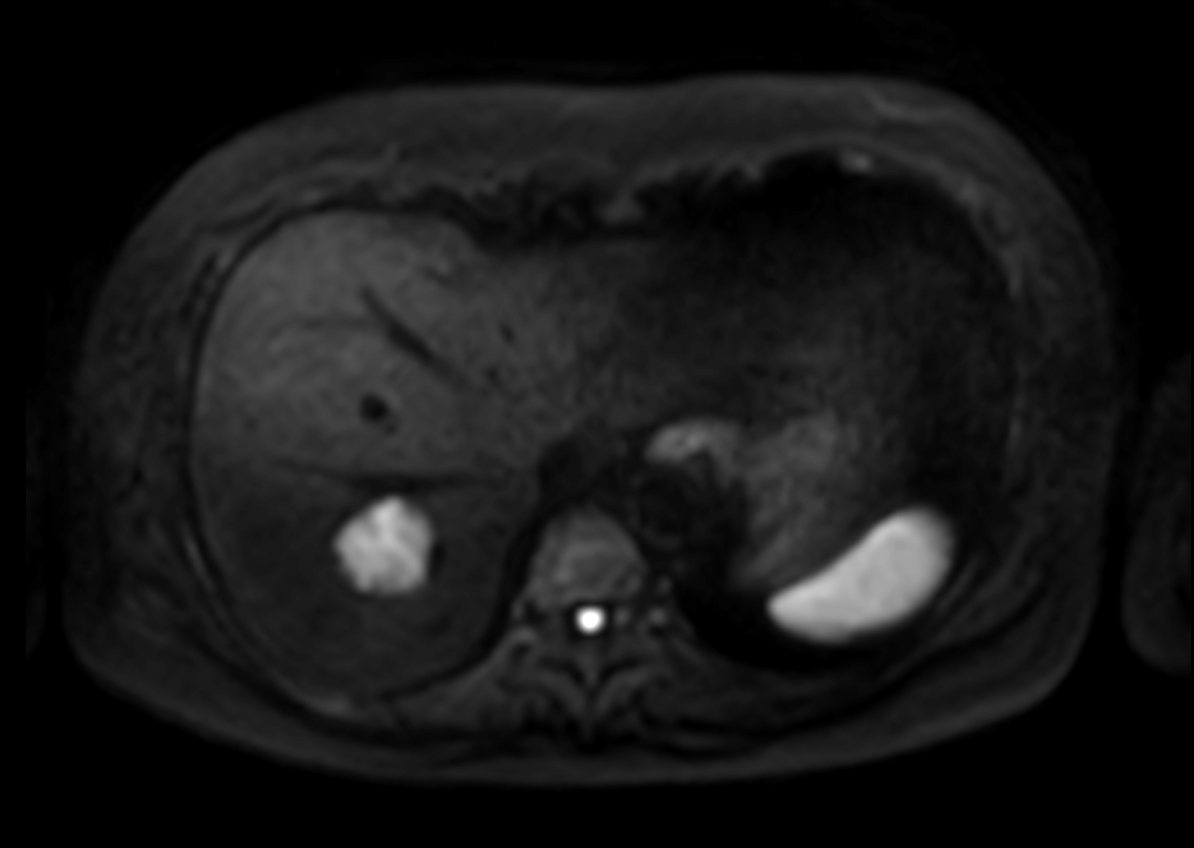

Axial DWI (b8, Black Blood)

Axial DWI (b1000)